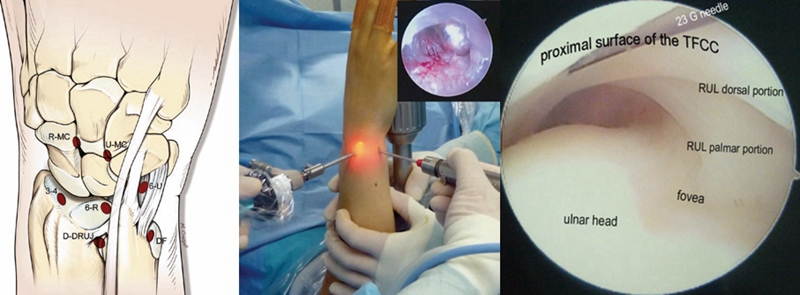

2.手术治疗

TFCCⅠ型损伤首选制动、理疗、口服非甾体抗炎镇痛药及关节腔激素注射等保守治疗,保守治疗超过3个月后无效行手术治疗。

ⅠA及ⅠD型损伤多采用清理、修整术;

ⅠC型若为孤立性撕裂,可单纯清创治疗,若为完全性撕裂,需手术切开修复;

ⅠB型损伤手术治疗多采用缝合修复术。

TFCCⅡ型损伤,对症状持续存在,经保守治疗无效者可行腕关节镜手术。

ⅡA、ⅡB、Ⅱc型损伤:腕关节镜下清创术及软骨成形术;若合并尺骨撞击或尺骨正变异者,行关节镜下清创术结合尺骨头部分磨除术(Wafer术)。

Case1

女性,42岁,右腕疼痛1年+,2020年4月手术。

影像学检查

关节镜视频

关节镜下清理后